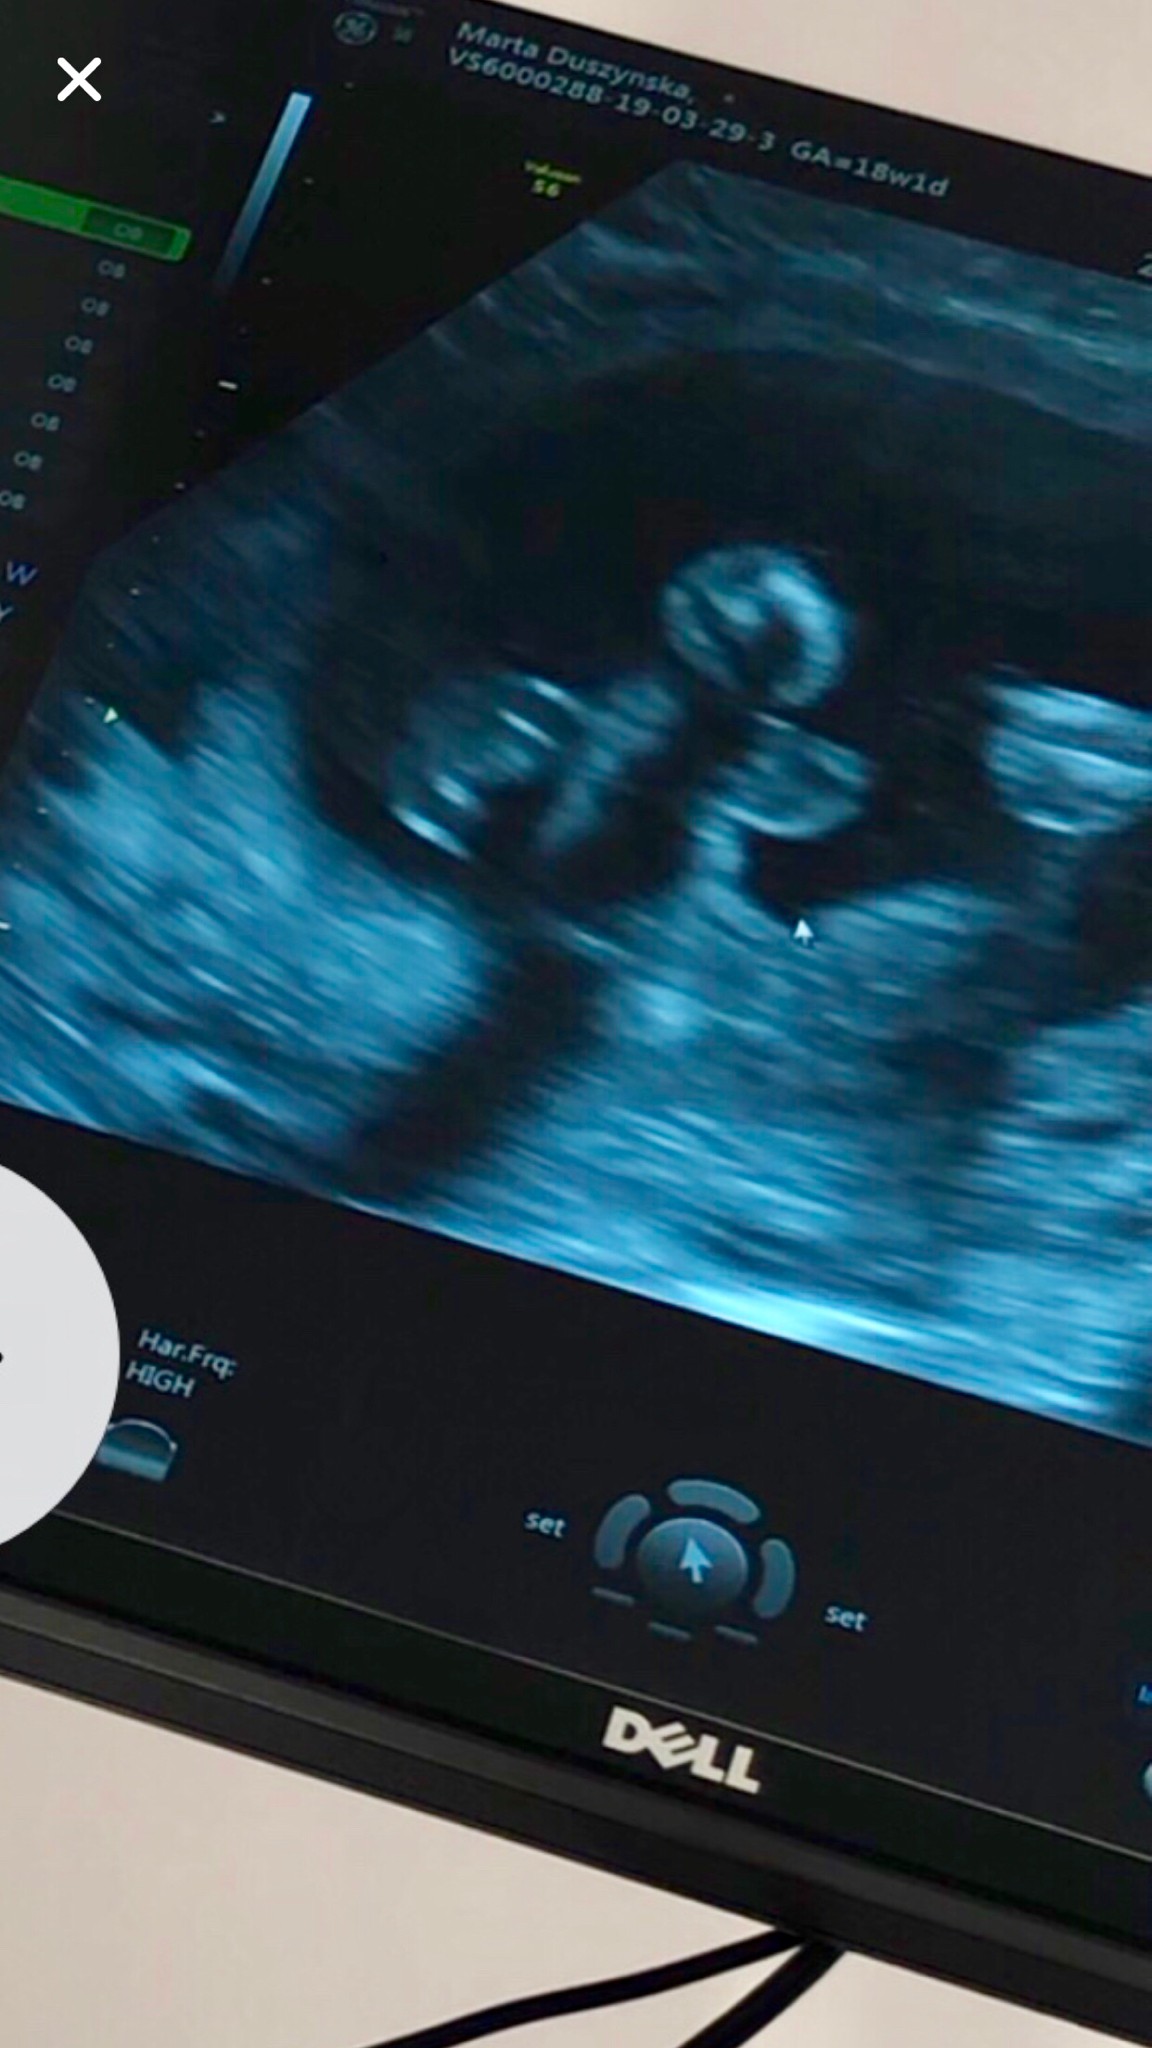

Oj oj czyżby była córeczka? No ja tam nic nie widzę sterczącego [emoji16] gratulacje!Laseczki z dzidzia ok. 100% pewności nie mam co do płci ale popatrzcie sobie i dajcie znać czy wy tez nie dostrzegacie jajec i siurka![]()

219g szczęścia. Szyjka 4,1cm